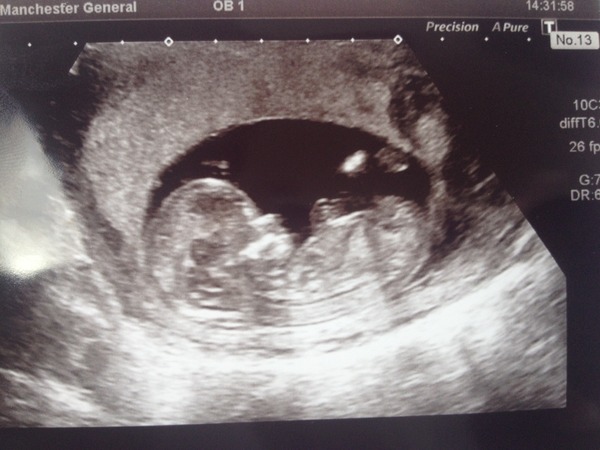

Blue beauliful scan picture Smile.

I had mine today, felt so relieved that baby is really there I cried. Then spent long time waiting to see midwife and consultant. I'll be taking aspirin to prevent high blood pressure and pre-eclampsia, anybody else?

Baby was wriggling so much Dr couldn't take second picture for nuchal measurement. But if I'm at risk they are going to ring me sometime next week. All in all good day Smile.

Yay Jucy lovely pic!

Look at your baby all stretched out & co-operative, the scanner kept huffing today because mine wouldn't take it's chin off it's chest

blue and jucy love your pics!

Lovely pics blue & jucy